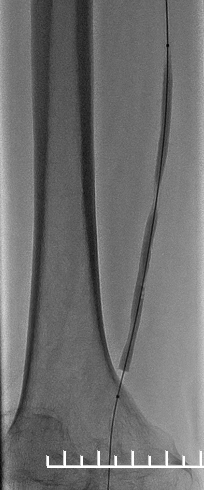

1.造影评估:左股动脉翻山入路,经鞘管造影见右股浅动脉中下段局限重度狭窄,远端股腘动脉、膝下动脉延迟显影,血流流速缓慢(图2,3,4)。

(图2)

(图3)

(图4)